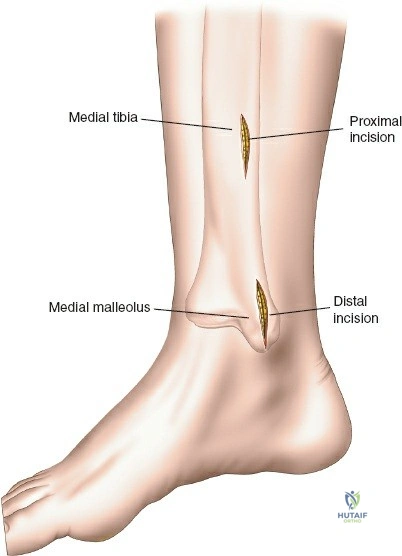

The minimally invasive distal tibia approach typically utilizes an anteromedial or direct anterior trajectory, prioritizing indirect reduction and subcutaneous plate insertion.

Incision Planning and Soft Tissue Dissection

- Incision Selection:

- Anteromedial Approach: Often preferred. A longitudinal incision, typically 3-5 cm, is made proximally and another similar incision distally (or a single longer incision) along the anteromedial aspect of the tibia. The proximal incision is placed away from the fracture zone and the distal incision is typically just proximal to the joint line, usually aligning with the non-articular part of the medial malleolus. The superficial peroneal nerve and saphenous nerve and vein must be identified and protected.

- Direct Anterior Approach: Can also be utilized, with incisions typically placed over the interval between the tibialis anterior and extensor hallucis longus muscles. The deep peroneal nerve and anterior tibial vessels lie deeper and must be protected.

- Subcutaneous Tunnel Creation: After skin incisions, subcutaneous dissection is performed to elevate skin flaps minimally. A submuscular or subcutaneous tunnel is then created, connecting the proximal and distal incisions. This tunnel should be just wide enough to accommodate the plate. Blunt dissection (e.g., using a blunt elevator, specialized plate insertion guide, or fingers) is critical to preserve the periosteum overlying the fracture fragments, which maintains their blood supply and vitality.